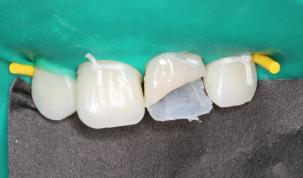

“旧冠再利用”术前牙冠大面积折断,露牙髓:

折断的牙冠:

根管治疗术前、术后:

根管治疗后牙冠重新粘接: